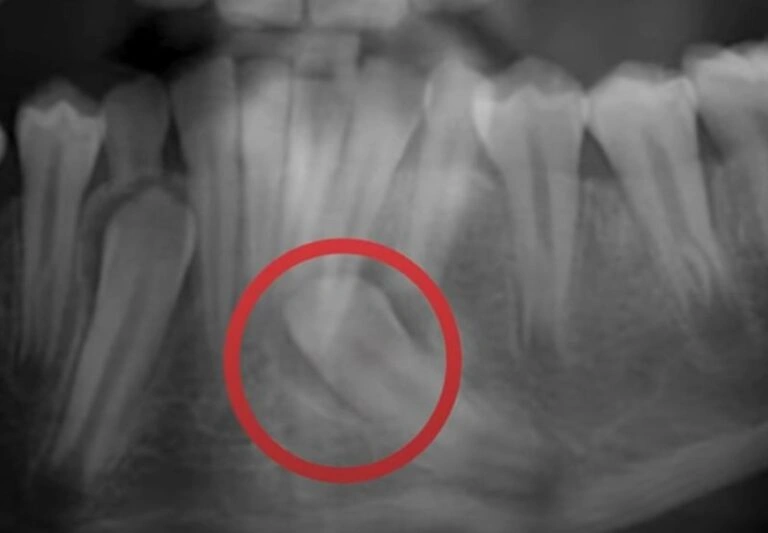

In some cases, the roots of the baby teeth don’t dissolve as they should, keeping them firmly in place. If the permanent tooth beneath isn’t growing in straight, it won’t apply enough pressure to push the baby tooth out. We often see this in kids with crooked or crowded teeth. A quick X-ray can tell us if this is the issue. See the case of Barret, a pediatric patient of mire below!

3. Crowding Issues

This is one of the most common reasons I see, and it’s something we should address early! If there isn’t enough space in your child’s mouth for their adult teeth to come in, the baby tooth can get stuck in place. As a result, the adult tooth might grow in behind or on top of the baby tooth, making things even more complicated.